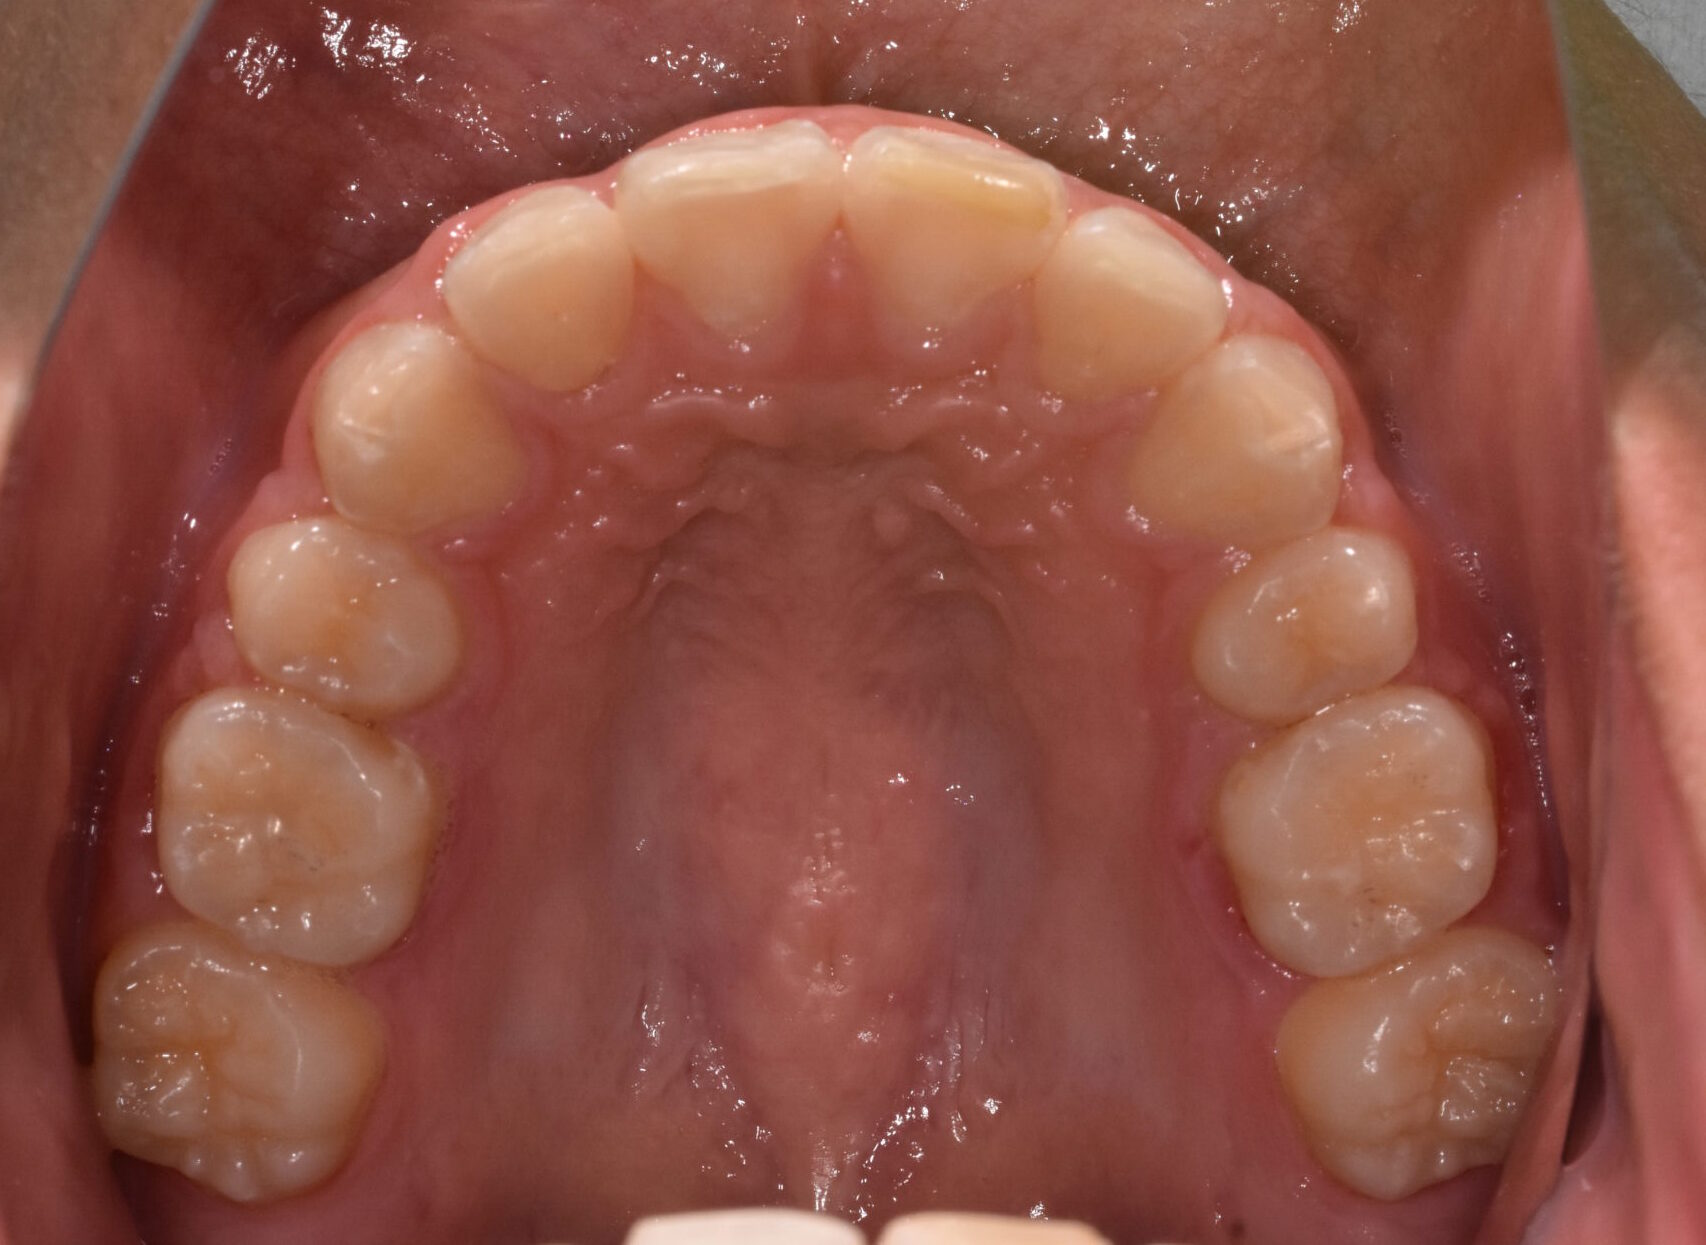

治療前

【診断】叢生、過蓋咬合

【治療方法】上下両側第一小臼歯抜歯、ワイヤー治療期間3年間、上顎口蓋にTPA(トランスパラタルアーチ)を行いました。